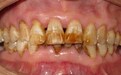

三、重度氟斑牙多数牙甚至全口牙出现黄褐色斑块,同时有线状、点状或窝沟状缺损,凹陷内有较深的染色,牙面失去光泽。